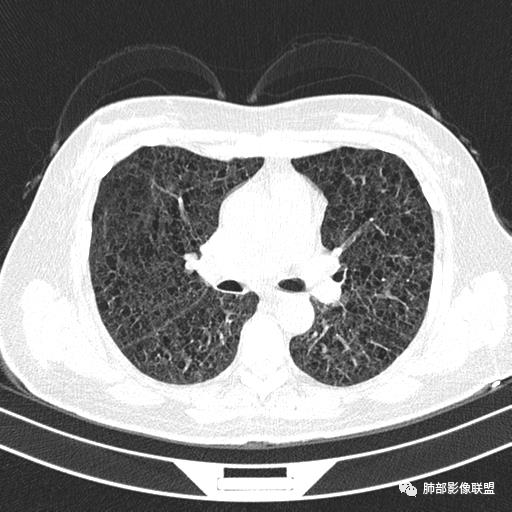

双肺弥漫囊腔,累及肋膈角,囊腔形态相对规则单一。

CT平扫示双肺弥漫分布大小不等囊状薄壁透光区,无内、中、外带分布差异,间质稍示增厚。拟LAM

中年女性育龄期妇女,咳嗽气喘,无吸烟史,有苯吸入史。影像:双肺弥漫均匀小囊腔,无明显分布优势,囊腔形态欠规则,壁薄,部分囊腔边缘血管征,伴双肺弥漫磨玻璃影,无结节,考虑lam,鉴别苯中毒肺损伤,囊腔多有分布优势,小叶中心分布为主,形态规整等

女,46,活动性气喘1年。苯吸入史半年。胸部CT:两肺弥漫囊腔,上至肺尖,下至肋膈角,形态类似小囊腔。考虑:LAM,鉴别LIP,BHD,PLCH等。

双肺弥漫大小不一薄壁含气囊腔,囊间肺组织正常,正常肺背景,肺尖肺底受累;青年女性,气喘,支持LAM

CT表现:双肺弥漫大小不等的薄壁囊腔,囊壁<2mm,外形规则,血管影多位于囊腔周围,囊腔之间肺组织正常,随着疾病进展到晚期,囊腔变大、增多,不可胜数,囊腔可融合成较大的囊,与肺气肿相似,形成间质性肺纤维化。部分病例可出现结节影。